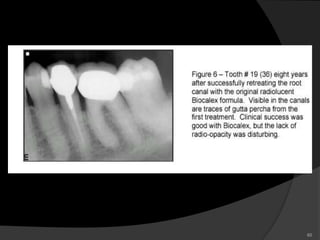

Calcium hydroxide based root canal sealers have been

disintegrated more rapidly than CRCS.

Root canal Sealer